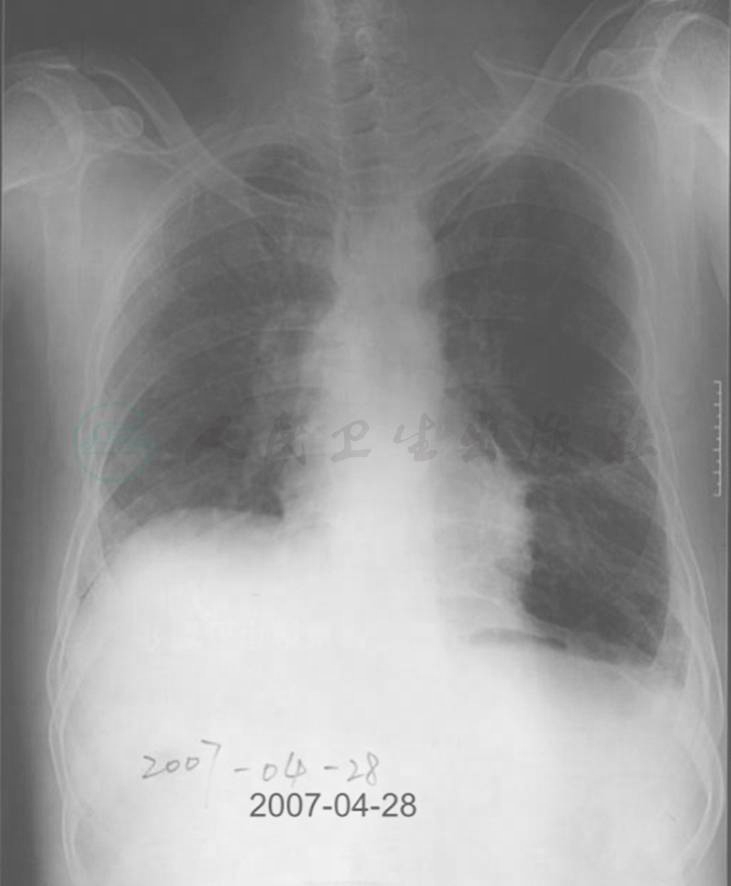

图5 10年前胸部X线表现

胸部X线可见右肺体积明显增大,透过度增加,而左肺体积相对缩小

图6 8年前胸部X线表现

胸部X线片可见右肺体积略有缩小,而左上肺体积明显增大伴多发大疱形成,肋膈角变钝,透光度明显增加